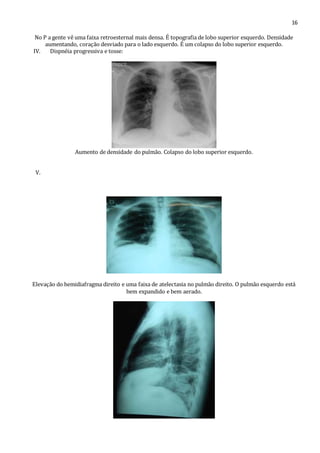

III. Sexo masculino, 34, com tosse e dispneia:

No P a gente vê uma faixa retroesternal mais densa. É topografia de lobo superior esquerdo. Densidade

aumentando, coração desviado para o lado esquerdo. É um colapso do lobo superior esquerdo.

IV. Dispnéia progressiva e tosse:

Aumento de densidade do pulmão. Colapso do lobo superior esquerdo.

V.

Elevação do hemidiafragma direito e uma faixa de atelectasia no pulmão direito. O pulmão esquerdo está

bem expandido e bem aerado.